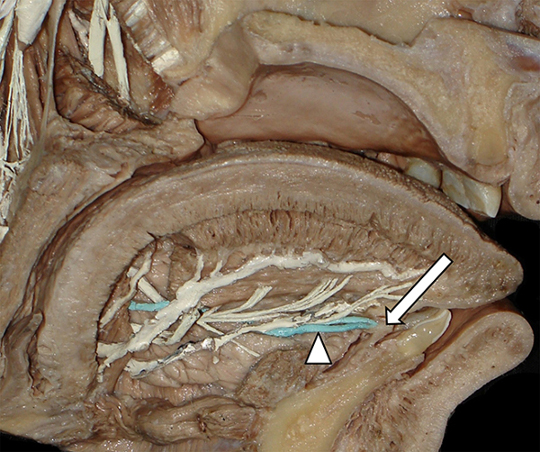

Preparado anatómico. Vista medial de la cavidad oral y piso de la boca. Se muestra el trayecto del conducto de Wharton izquierdo (coloreado en celeste), en el piso de la boca que termina en el orificio umbilical homolateral (flecha larga). Nótese la existencia del conducto sublingual mayor (cabeza de flecha), acompañándolo en su sector distal.